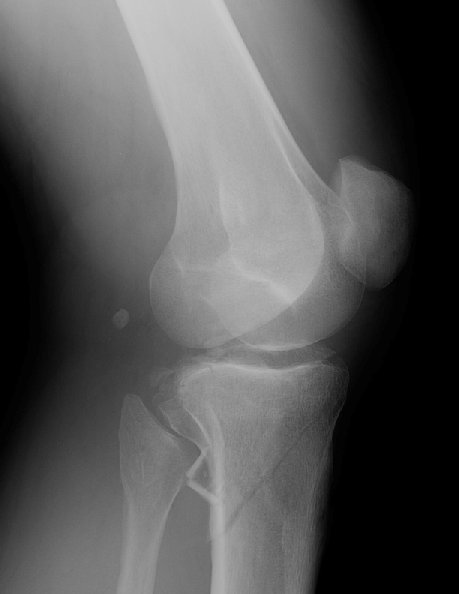

Return to Tibial Plateau Fracture